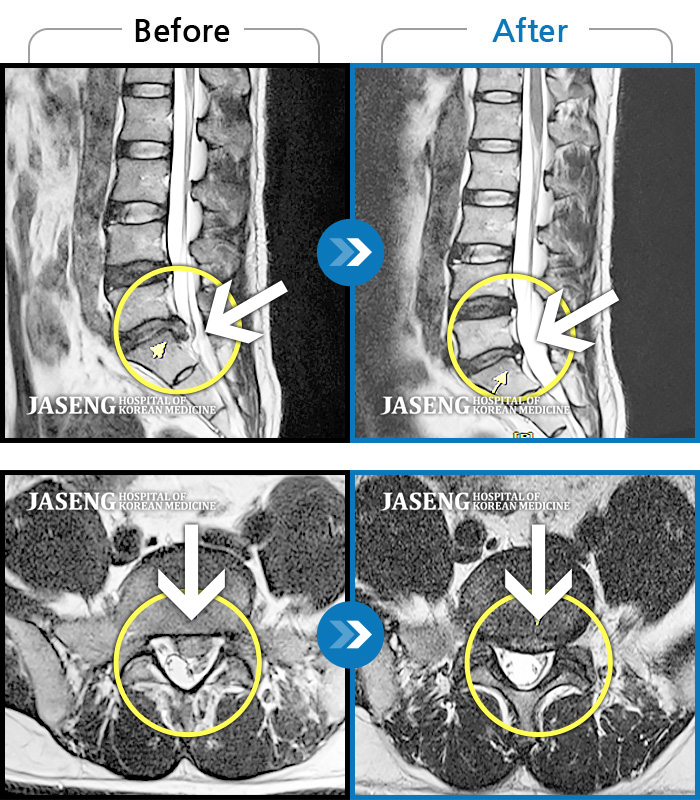

허리디스크

광주 · 김준수 원장

좌측 허리부터 골반 통증, 좌측 다리까지 이어지는 저림

촬영시기

2023.03.08 ~ 2024.08.31

2024.09.10

조회수 10,816